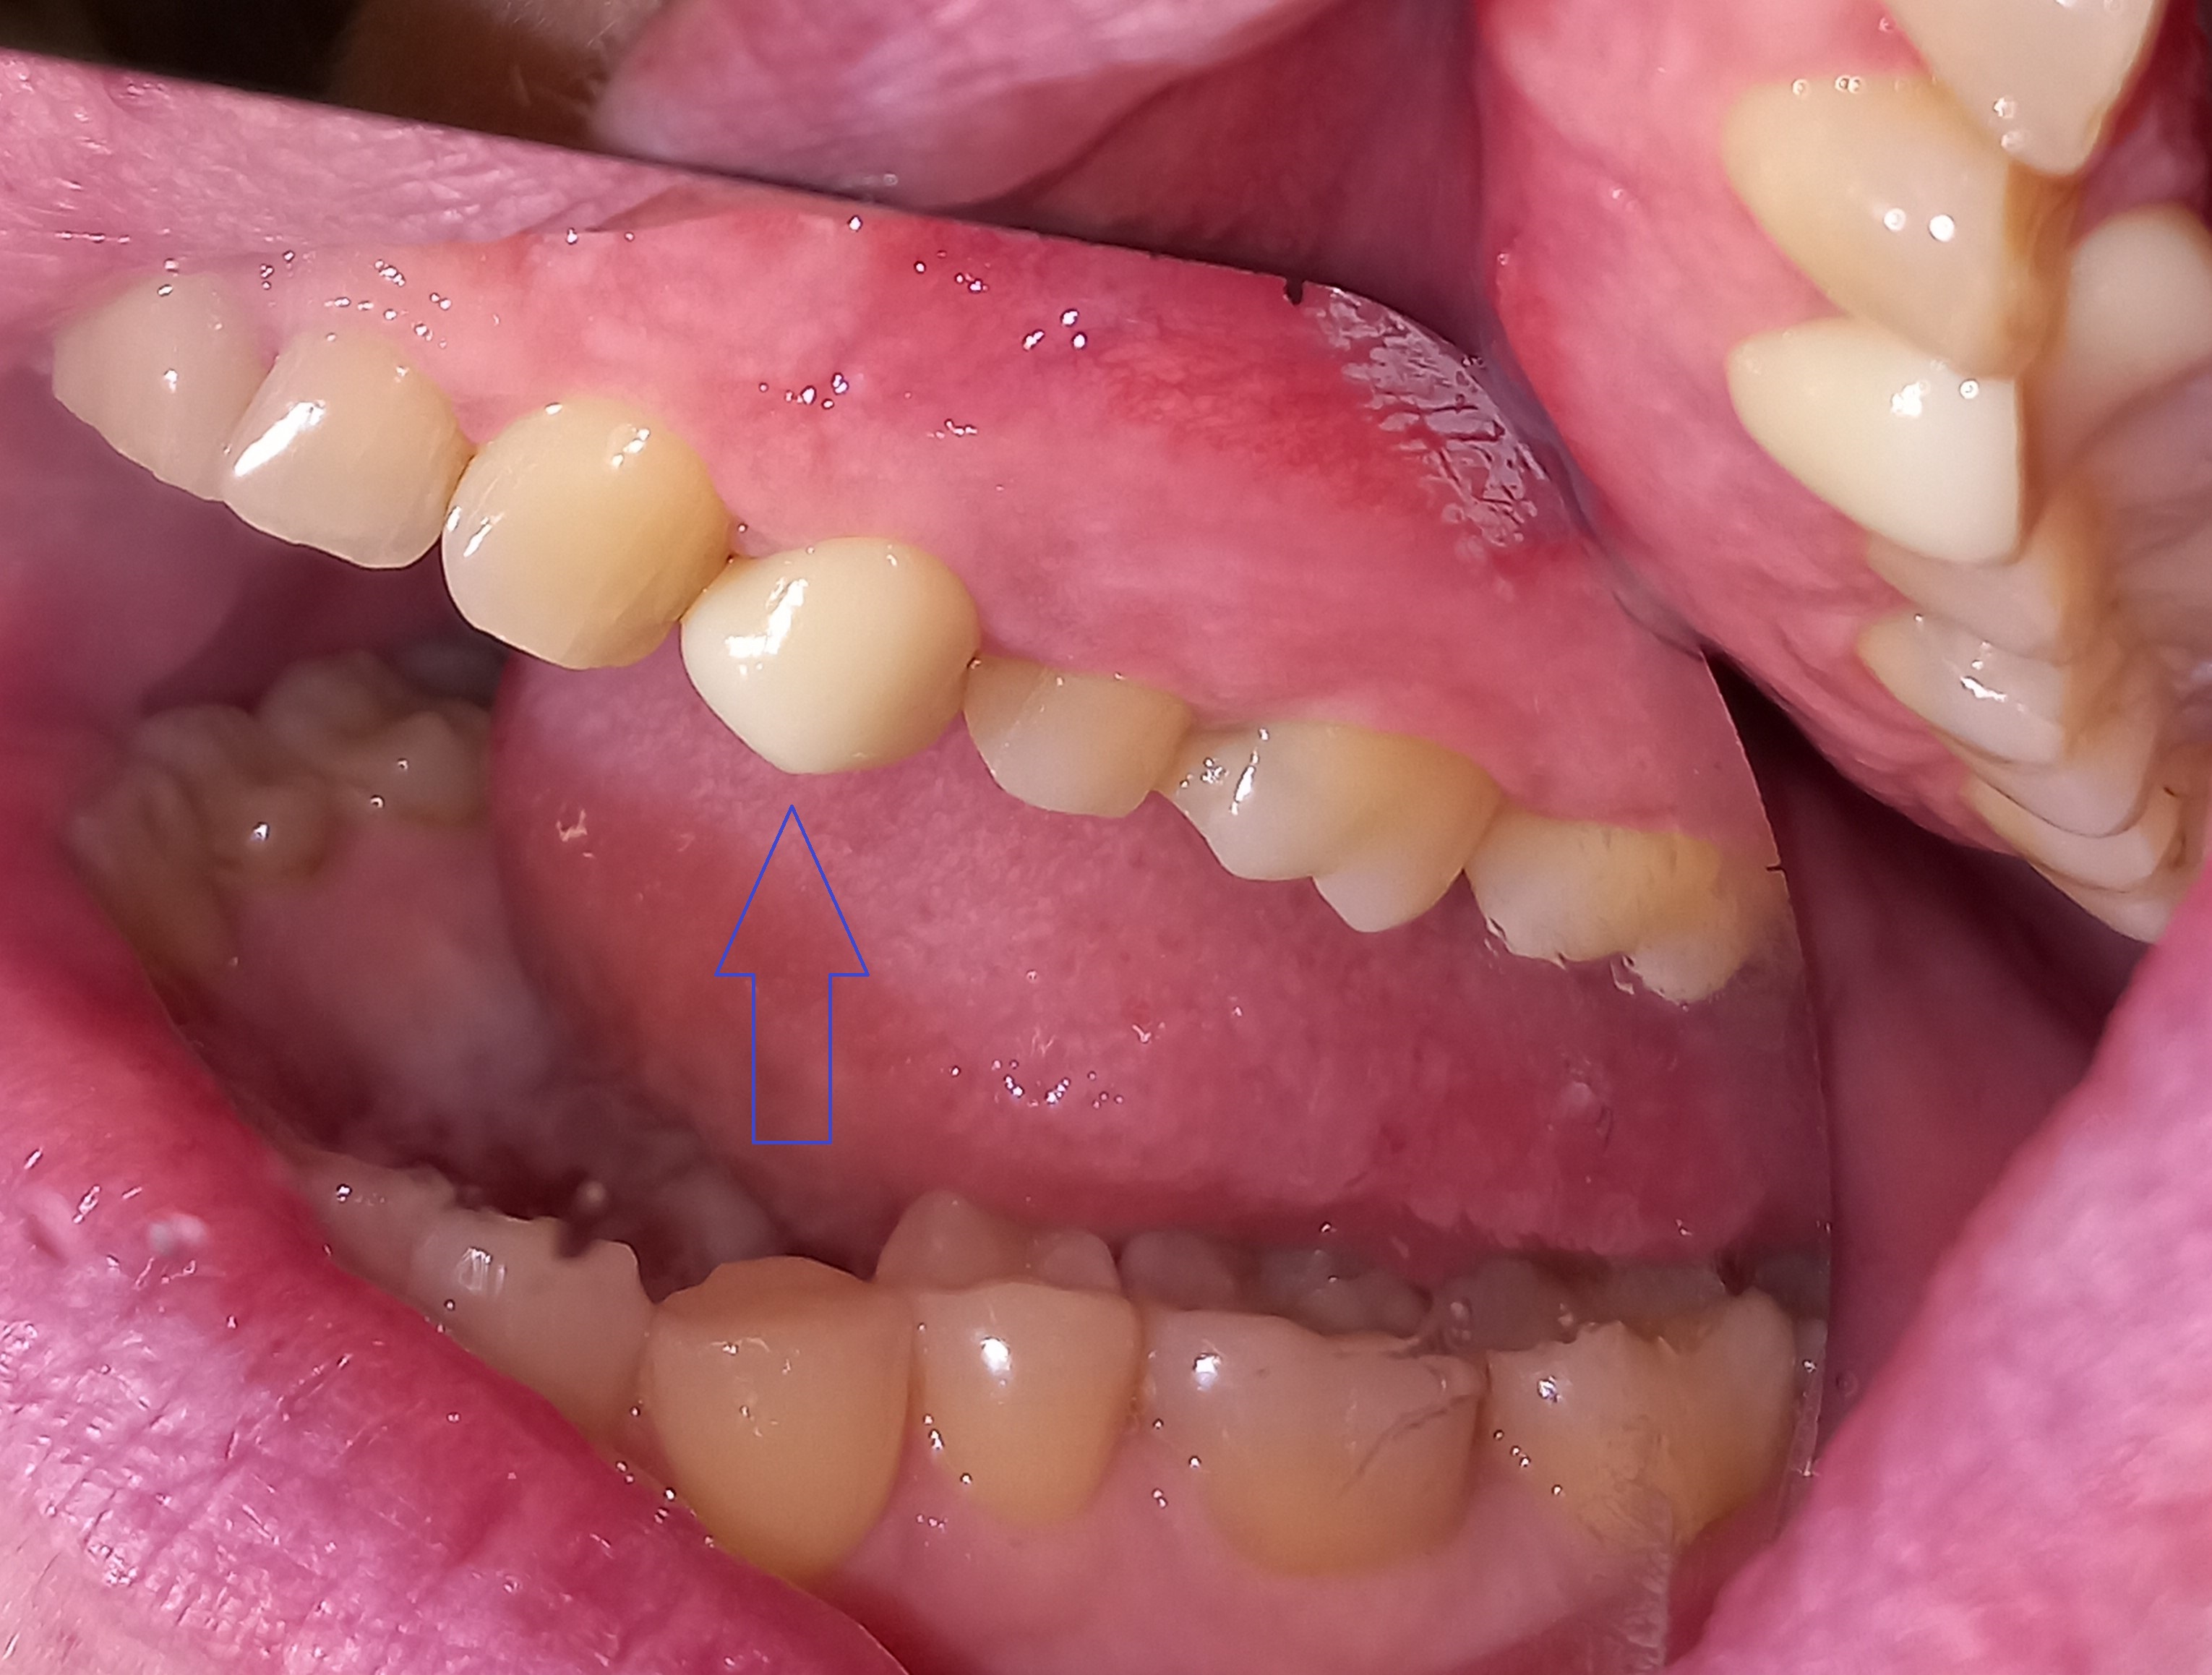

Η ασθενής έχασε το δεύτερο αριστερό γομφίο της κάτω γνάθου. Δεν επιθυμούσε να τοποθετήσει εμφύτευμα στην περιοχή, γιατί φοβόταν τη χειρουργική διαδικασία. Σε συνεργασία με τον οδοντοτεχνίτη αποφασίστηκε η κατασκευή μιας ολοκεραμικής θήκης, η οποία θα είχε ένα επιπλέον γομφίο “κρεμαστό” . Η συγκεκριμένη προσθετική αποκατάσταση αποτέλεσε μία εναλλακτική λύση θεραπείας στο πρόβλημα της ασθενούς, προκειμένου να αποφύγει τη χειρουργική διαδικασία του εμφυτεύματος.

ΠΡΙΝ

ΜΕΤΑ